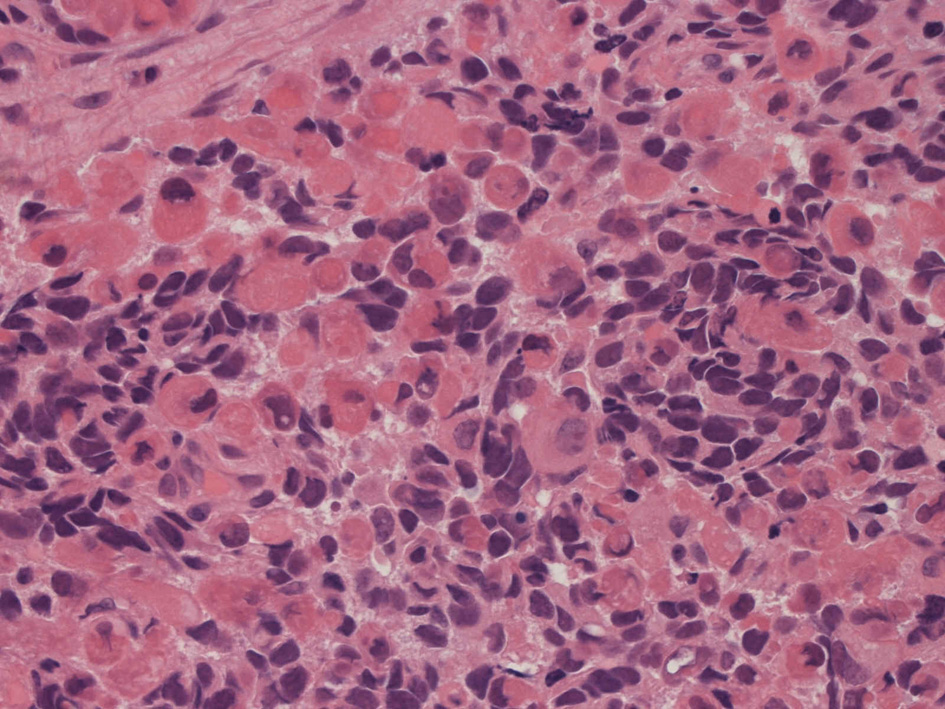

病理組織所見

small round cell tumorの中でrhabdomyosarcomaは腫瘍細胞に種々の抗原が陽性となるため診断を誤ることがあり注意が必要である*1

*1 Bahrami A, et al., Aberrant expression of epithelial and neuroendocrine markers in alveolar rhabdomyosarcoma: a potentially serious diagnostic pitfall. Mod Pathol. 2008 Jul;21(7):795-806. Epub 2008 May 16. PMID:1848799199